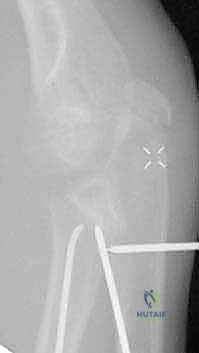

كسر عنق الكعبرة من النوع الثاني (Salter-Harris type II) مع إزاحة واضحة في منطقة الكردوس بالنسبة للمشاشة، وهي حالة تتطلب تقييماً دقيقاً من قبل خبير مثل الأستاذ الدكتور محمد هطيف.

صورة شعاعية توضح كسراً من الدرجة الثالثة يتطلب تدخلاً دقيقاً لإعادة الرأس الكعبري إلى مساره التشريحي.